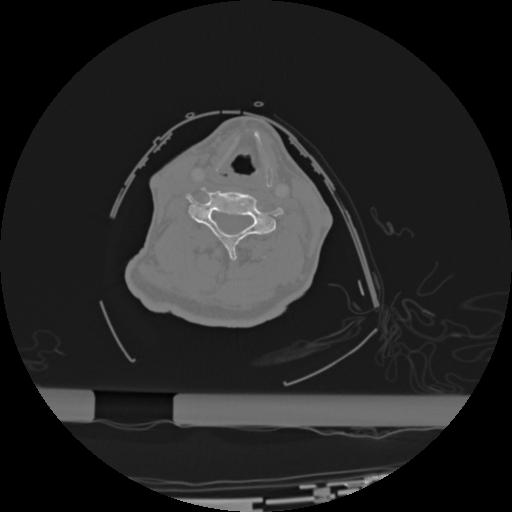

22 ANGIO,CE,Vol,0.5,ANGIO,,